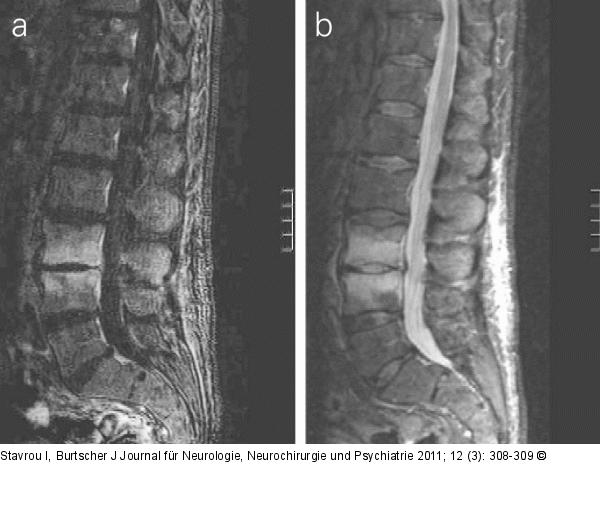

Abbildung 1a-b: Wirbelkörper - MRT MRT 1,5 Tesla, (a) sagittale T1-gewichtete Sequenz nach Kontrastmittelgabe mit Subtraktion sowie (b) T2-gewichtete Sequenz: Kontrastmittelannahme der Wirbelkörper L3/L4 begleitet vom massiven Knochenmarksödem, 2 Wochen vor der X-LIF-Operation. |

MRT 1,5 Tesla, (a) sagittale T1-gewichtete Sequenz nach Kontrastmittelgabe mit Subtraktion sowie (b) T2-gewichtete Sequenz: Kontrastmittelannahme der Wirbelkörper L3/L4 begleitet vom massiven Knochenmarksödem, 2 Wochen vor der X-LIF-Operation. |